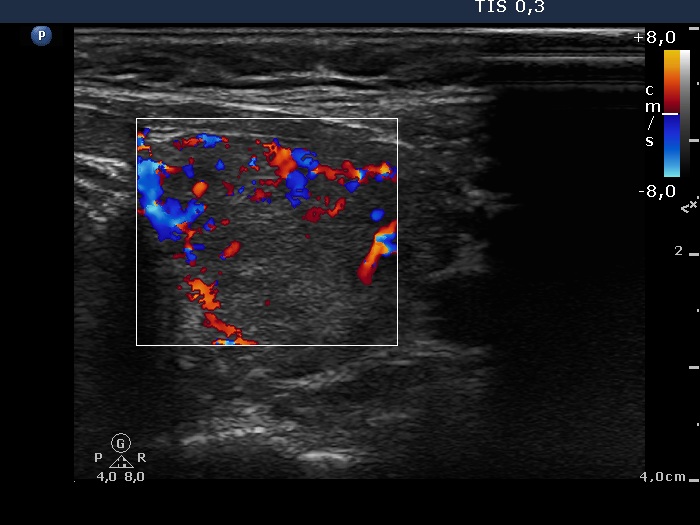

Consecutively operated patients with autoimmune thyroid disease - case 44 (1755) (ultrasonographic picture 6)

Left lobe, transverse scan, color Doppler mode. The vascularization is increased.